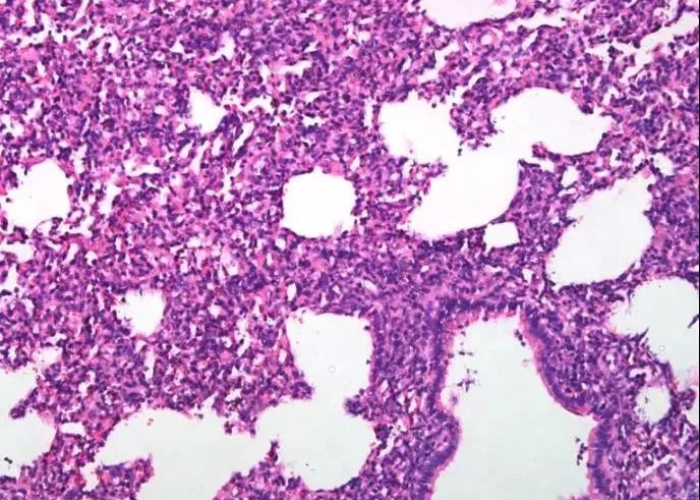

特征性肺部听诊音

约50%的早期患者在肺部听诊时可闻及Velcro啰音( Velcro crackles),这种声音类似于撕开尼龙扣时的细微爆裂音,这是肺泡壁增厚和间质水肿的典型表现,但需要专业医生通过听诊器才能识别。 -